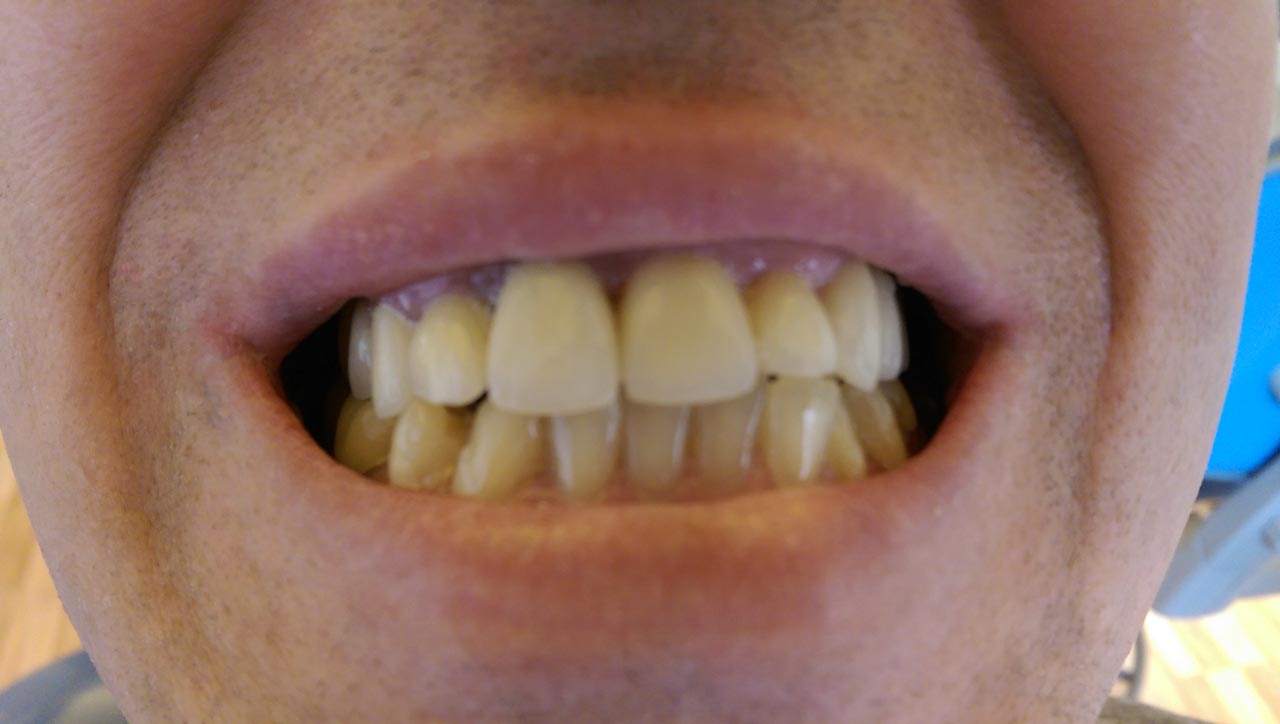

Alsó állcsont teljes rehabilitációja 72 óra alatt, azonnal terhelhető implantátumokkal súlyos paradontitisben szenvedő dohányzó páciens esetében. Az alsó állcsont fogai mind mozogtak az előrehaladott fogágypusztulás miatt.

A fogakat eltávolítottuk, a gyulladt, fertőzött csontot kitakarítottuk, kifertőtlenítettük, majd azonnal implantáltunk.

Svájci, IHDE márkájú, azonnal terhelhető implantátumokat helyzetünk be, és ezekre harmadnapra rögzített, hosszútávú, fémvázas, esztétikus műanyaggal leplezett hidat ragasztottunk be.

Ezt az ideiglenes hidat a sebek gyógyulása miatt használjuk, de tartóssága miatt véglegesként is használható. A legtöbb esetben, ahogy itt is, 6 hónap múlva porcelán hídra cseréljük, a teljes gyógyulás után.